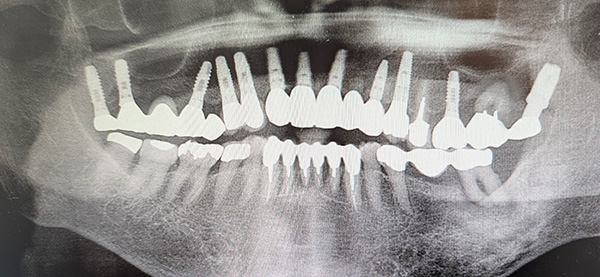

インプラントの長期症例

掲載写真撮影:2025年(85歳/女性)

上顎インプラント:2001年(年前)インプラント埋入 当時61歳

上顎には、左上に2歯しか存在せず大きな義歯が装着されており、永年にわたり違和感及び咀嚼に苦痛を感じ、取り外しをしなくて良い方法はないかと来院されました。

下顎は、特に前歯には、歯周病及び虫歯が多数あり歯周治療の後に審美回復も希望されセラミックを装着しました。

上顎は、インプラント治療を行い、以後、衛生士による年3回の定期的な口腔ケアのみで、24年が経過しましたが歯肉及びインプラントを支える骨にも全く問題なく、発音及び審美的にも満足され快適な食生活を過ごされています。